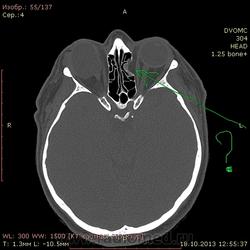

52 года. По направлению от невролога после травмы от 13.10. Правый глаз - посттравматические изменения(травма в детстве).

Интересует ваше мнение по поводу медиальной стенки левой глазницы - что за дефект? чего-то растет или последствия старой травмы или вариант нормы?

Или стенка все-таки без дефекта, а просто таким образом деформирована?

Считаю, что слева - это последствия "старой" травмы, т.н. взрывного (blowout) перелома медиальной стенки орбиты.